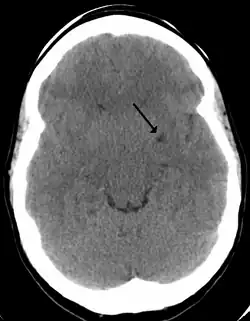

![]() A perivascular space as seen on CT | |

A perivascular space, also known as a Virchow–Robin space, is a fluid-filled space surrounding certain blood vessels in several organs, including the brain,[1] potentially having an immunological function, but more broadly a dispersive role for neural and blood-derived messengers.[2] The brain pia mater is reflected from the surface of the brain onto the surface of blood vessels in the subarachnoid space. In the brain, perivascular cuffs are regions of leukocyte aggregation in the perivascular spaces, usually found in patients with viral encephalitis.

In humans, perivascular spaces surround arteries and veins can usually be seen as areas of dilatation on MRI images. While many normal brains will show a few dilated spaces, an increase in these spaces may correlate with the incidence of several neurodegenerative diseases, making the spaces a topic of research.[4]

Perivascular spaces are most commonly located in the basal ganglia and white matter of the cerebrum, and along the optic tract.[13] The ideal method used to visualize perivascular spaces is T2-weighted MRI. The MR images of other neurological disorders can be similar to those of the dilated spaces. These disorders are:[7]

Perivascular spaces are distinguished on an MRI by several key features. The spaces appear as distinct round or oval entities with a signal intensity visually equivalent to that of cerebrospinal fluid in the subarachnoid space.[7][14][15] In addition, a perivascular space has no mass effect and is located along the blood vessel around which it forms.[14]